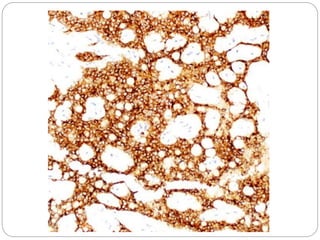

• #23 Immunohistochemistry for β-catenin shows nuclear and cytoplasmic staining in > 90% of tumors.

• #25 Immunohistochemistry for CD10 shows cytoplasmic staining in solid-pseudopapillary tumors in nearly all the cases. Perinuclear staining may be seen in some instances.